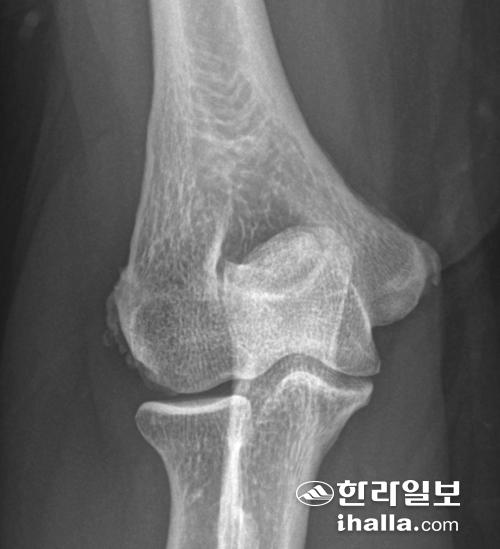

▶검사 소견=단순 방사선검사는 대부분 정상이나 유리체, 관절염, 박리성 골연골염 등과 감별하는데 도움이 될 수 있다.

주관절 방사선 사진. 외측 및 내측 상과에 석화화 병변(calcification)이 보인다.

경우에 따라 외상과 부위에 석회화가 관찰되기도 한다. 초음파 또는 자기공명영상(MRI)은 총신전건의 비후, 건실질 내 파열, 퇴행성 변화 및 석회화 등을 확인할 수 있다. 자기공명영상(MRI)을 통해 동반된 관절 내 병변 등을 추가적으로 확인할 수 있으나 증상의 중동도와는 관련성이 크게 없으며, 수술의 예후를 판단하는데도 제한적이다.